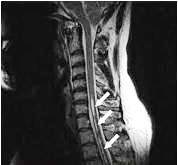

Dijagnoza – Osim na kliničkoj slici, dijagnoza siringomijelije se zasniva

na savremenim metodama slikanja nervnog tkiva. CT može biti od pomoci,

ali je snimanje NMR-om metoda izbora, jer može da predstavi uzdužni presek

kičmene moždine i moždanog stabla. U odstustvu ovih metoda, nalaz artropije

na cervikalnoj kičmi, na nativnom rendgenskom snimku, može da ide u prilog

dijagnoze siringomijelije. Mijelografija se danas ređe koristi; ona prikazuje

deformitet ili blok kontrasta.